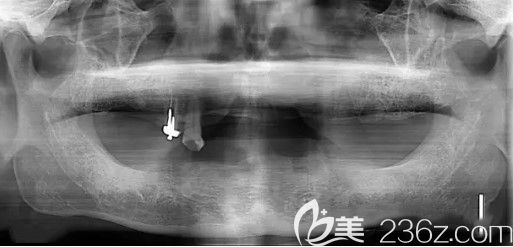

【我种牙前的 CT片,全口牙缺失,医生说我骨量不足】:

来天津中诺口腔医院,孩子们找的是张喜明医生,经过检查,医生说我的牙槽骨萎缩了,和孩子们商量后,决定的种牙方案是——立得用种植体系。